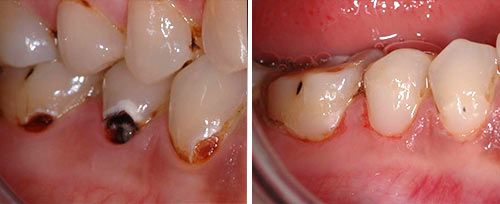

Carious Dentine Removal

Courtesy of: Ivica Anić, DDS, Ph.D.

Laser source: Er:YAG (2940 nm)